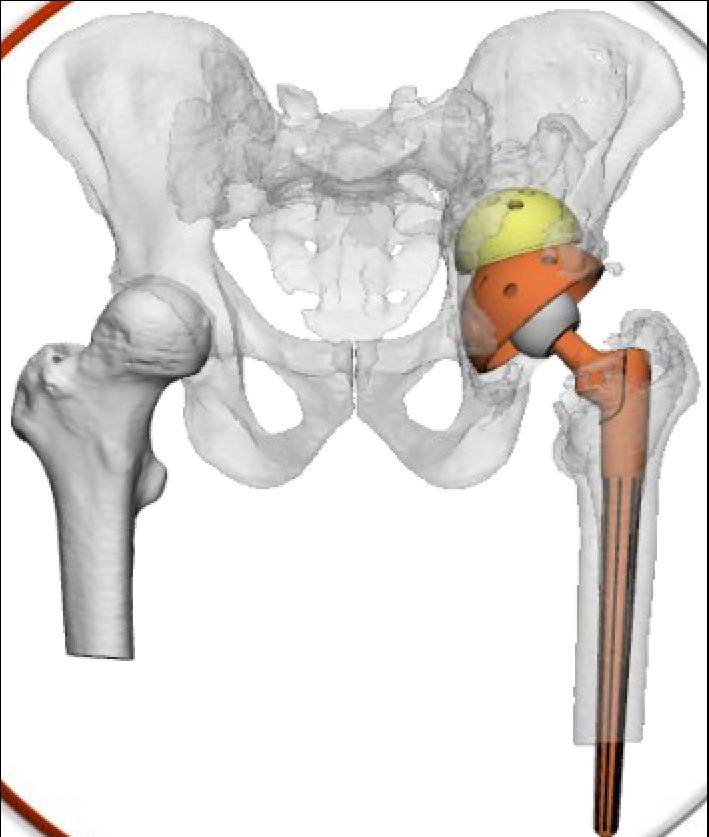

衡东县中医院放射科GE64排CT机扫描后给厂家提供3D打印数据模块:

放射科怎么打印放射科新技术助力3D打印精准置换——记一例人工髋关节置换术后假体脱位患者的个性化治疗_https://www.jmylbn.com_新闻资讯_第7张